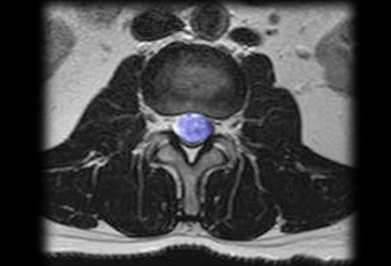

وی در ادامه افزود: تومور تعدادی علائم اختصاصی دارد که به طور معمول در اثر معاینه اختلالات عصبی میتوان محل تومور و نوع آن را مشخص کرد که با عکسبرداری و ام آرای میتوان تومور را تشخیص داد.